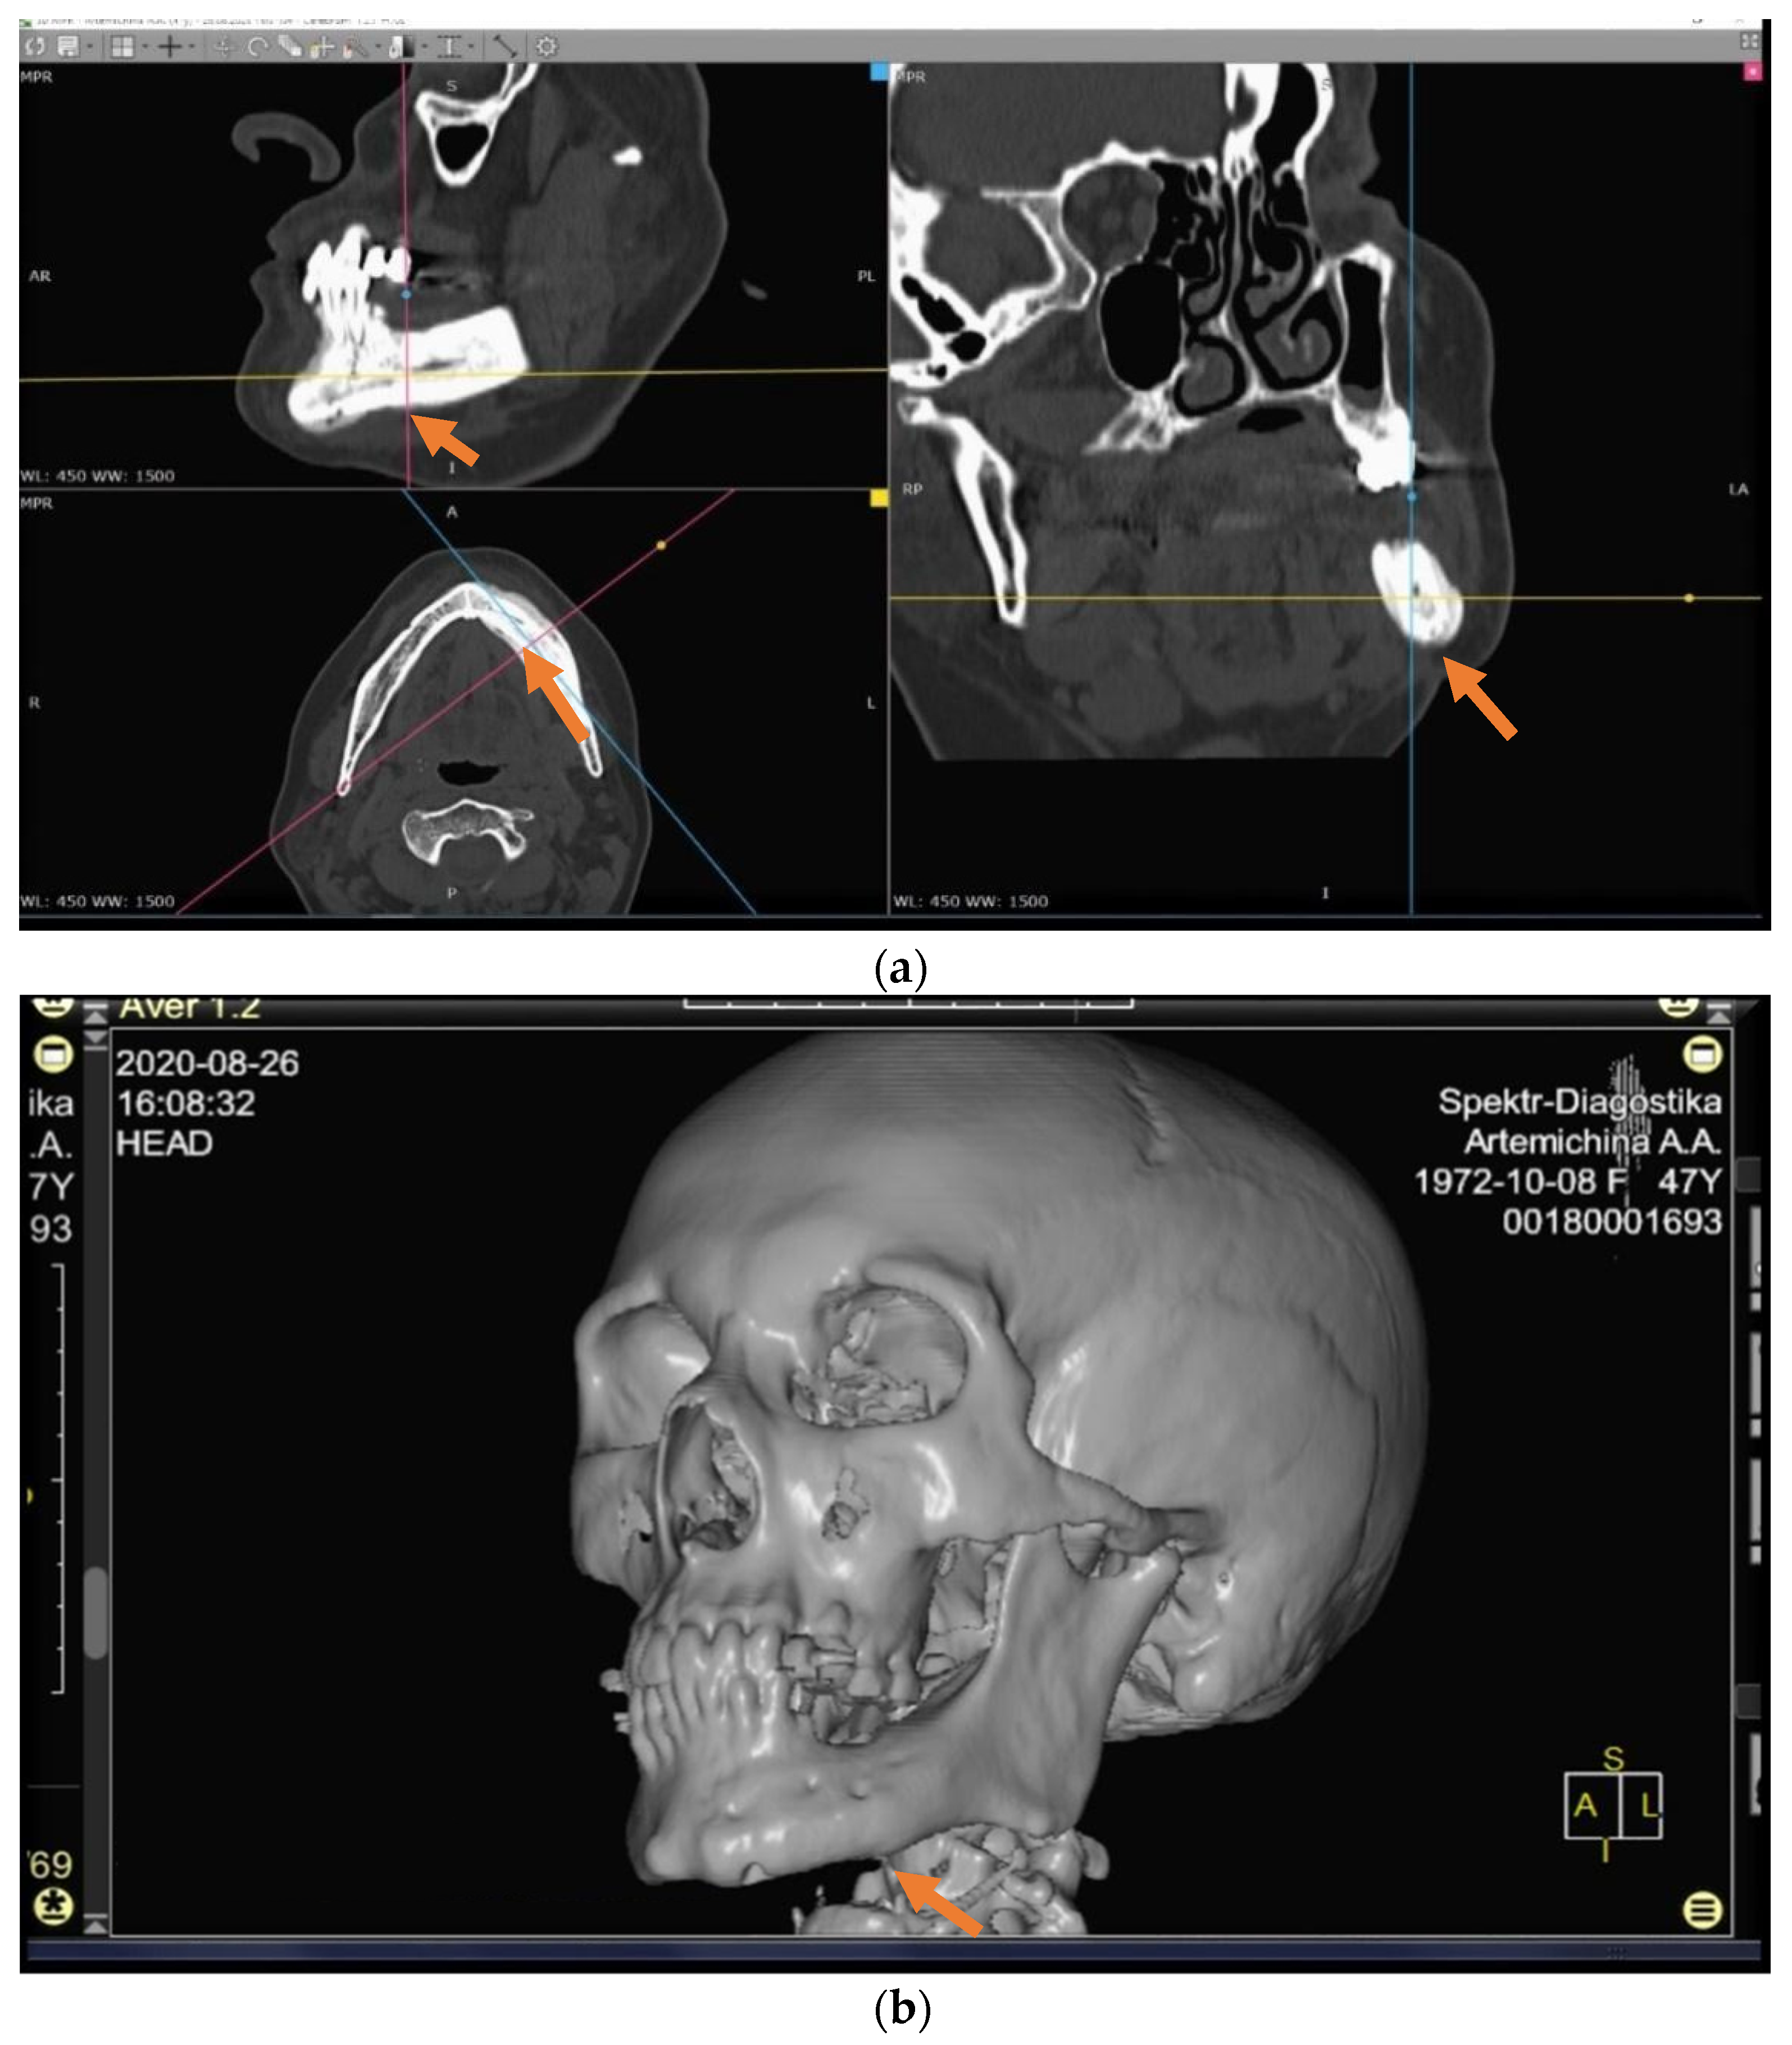

The patients in the main group (43 subjects) underwent segmental resection of the jaw after preoperative preparation (Figure 2 and Figure 3a,b).

An analysis of the results obtained from the Numeric Pain Rating Scale demonstrated that the mean pain intensity before treatment was 8.9 points in the control group, and 9.7 in the main group (Figure 4). These values are indicative of “unbearable pain.” After treatment (30 days), the pain score in the control group decreased and amounted to 4.1; this is evidence of the persistence of “moderate pain” in the patients. In patients who underwent segmental jaw resection (Figure 5a,b and Figure 6), the mean pain intensity was 0.5. There was no relationship with gender, but there was a direct relationship between the intensity of the pain and the stage of the process (CI = 95%).

Table 3 presents the results obtained with the Visual Analog Scale in patients with MRONJ after six months, which make it possible to assess changes in this parameter over time. After treatment, this parameter value was 3.6 in the control group and 0.1 in the main group (Figure 7a–d).

In the patients in the main and control groups, the pain intensity index values before treatment approached similar values. After surgery, the pain intensity index in the main group was close to normal values. In the control group, 30 days after conservative treatment, there was a tendency for the parameter to decrease; however, after six months, it did not reach the “no pain” mark (Figure 8 and Figure 9a,b).

Figure 1. (ad) Patient A: 47-year-old female. DS: Medication-related osteonecrosis of the jaw (the left side). Surgical treatment: Resection of the lower jaw on the left (9 September 2018).

Figure 8. CT scan three years after the surgery.